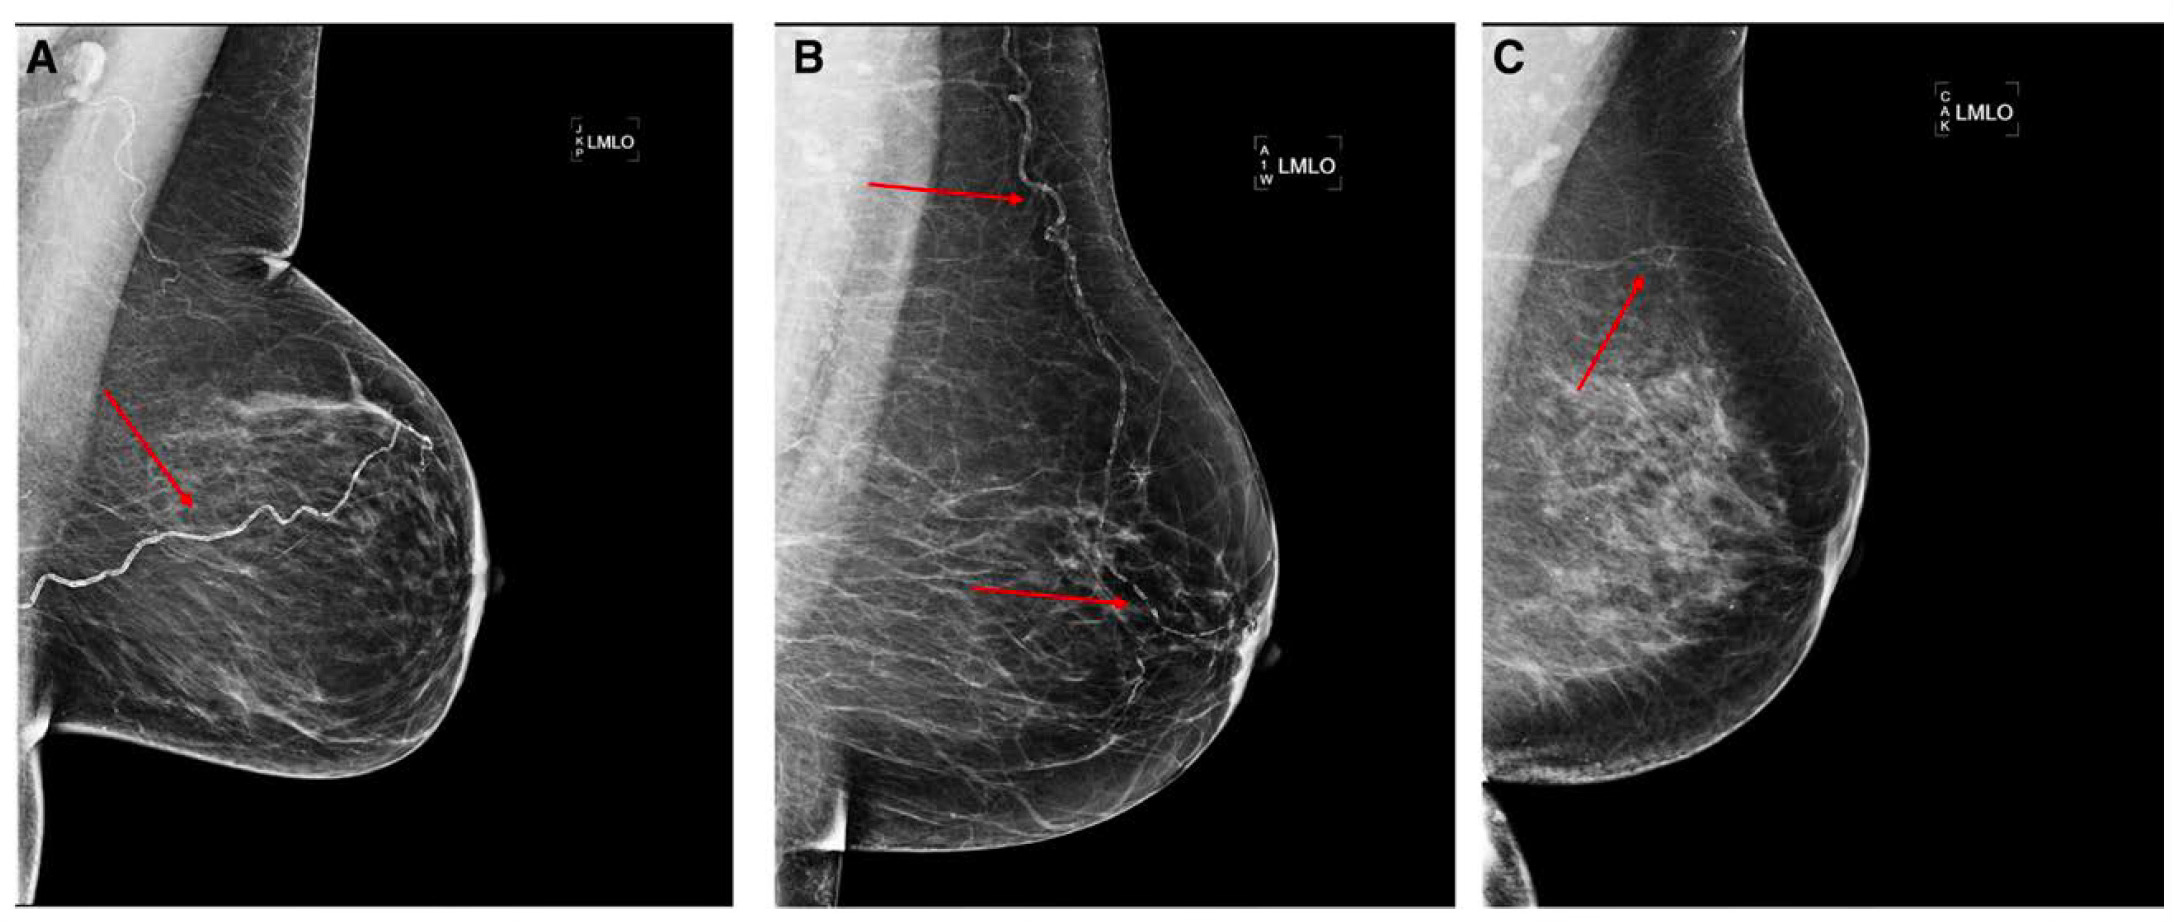

With that background, let’s go on to the landmark MASAI trial results, initially reported last year. This trial used the Transpara algorithm, developed by ScreenPoint Medical in The Netherlands, with 2D mammography. Subsequently, on 30 January 2026 the two-year follow up was published. The Table below summarizes the main results for both reports.

From the screening phase, there was a 29% increase in detection of cancer with AI, with a 24% increase in invasive cancer. There was no significant difference in the recall rate. The false positive rate was 1.4% in both arms of the trial. There was a 44% reduction in screen-reading workload.

At 2-year follow up, there was 12% less interval cancer detected in the AI arm, and the cancers picked up by AI were smaller, less aggressive: 16% reduction of invasive cancers and a 27% reduction of non-luminal A subtypes (including triple-negative and HER2-positive cancers). Accordingly, the AI support served a preventative role for earlier detection, catching aggressive breast cancer at the time of screening. But there is more to AI and prevention as we’ll get to in the next section. Of note, the Transpara algorithm is being used in 2 other large randomized breast cancer screening trials: in Norway, a trial of 140,000 women, called AIMS and in the US with 400,000 women, known as PRISM.